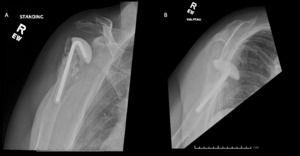

A 69-year-old woman presented after resection arthroplasty of her right shoulder hemiarthroplasty and completion of antibiotic treatment for culture negative PJI for evaluation of reconstructive options. She had a history of a displaced two-part right proximal humeral fracture which was repaired with an intramedullary nail. Post operatively, she had persistent pain and CT scan of the shoulder showed two screws in the humeral head that extended through the cortex and into the glenohumeral joint. The screws were removed and replaced with smaller screws. Subsequently, she had non-union of the fracture in the setting of deltoid weakness and was revised to a right hemiarthroplasty (Figures 1-3). Post operatively, she had persistent pain refractory to physical therapy and diminished function that was impacting her quality of life. She sought subsequent care, and there was concern for arthroplasty failure secondary to a septic versus aseptic condition and the decision to proceed with resection arthroplasty was made. During resection arthroplasty, a significant amount of fluid was expressed from the joint space. The combination of the clinical picture of progressive and persistent pain and the gross expression of fluid were concerning for PJI and the decision to treat was made. It was felt that the extent of humeral bone loss did not allow for a stable cement spacer, so none was placed. Intraoperative joint fluid cultures, anaerobic, and fungal cultures were all negative for growth. Cultures were held for 21 days to rule out C. Acnes infection. Considering the plan for future reimplantation, infectious disease consultation recommended a 6-week course of vancomycin but after 2 days the patient had a transfusion reaction and was switched to daptomycin. She was left with markedly limited active motion associated with severe pain. After completion of the antibiotic course, the patient elected to proceed with revision surgery. This patient had a flattened and distorted glenoid and atrophied rotator cuff musculature demonstrated prior to resection arthroplasty on CT (Figure 4). This patient’s prior hemiarthroplasty had been a tantalum coated, cemented humeral stem with associated marked thinning of the humeral cortex even prior to resection arthroplasty, and this resulted in a large amount of proximal humeral bone loss during the resection (Figure 5). The patient was severely debilitated by the right shoulder and wanted to proceed with reconstruction. Because of the combination of glenoid and humeral bone loss and the lack of rotator cuff attachments, a custom constrained prosthesis design process was initiated, and the implant was available 16 months after the resection arthroplasty. Preoperative 3 phase SPECT (Single Photon Emission Computed Tomography) three phase bone scan, upper extremity CT, and blood work (WBC 5.4, ESR 9, CRP 0.8) showed no suggestion of active infection.